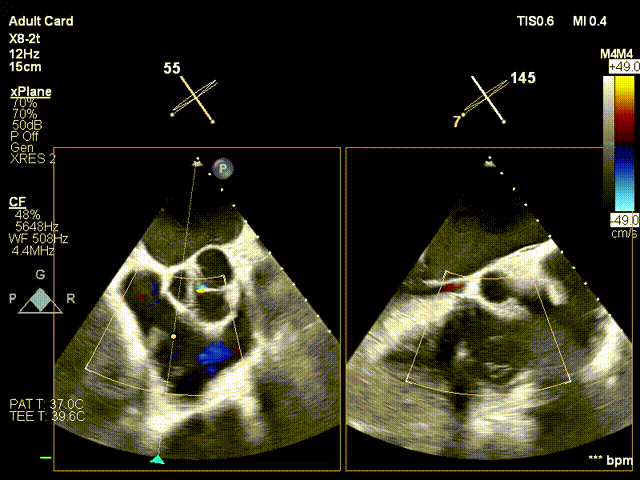

1. Preoperative baseline regurgitation

2. Steer and rotate the delivery system toward the target; advance and deploy the anchoring screw under 3D MPR plane guidance